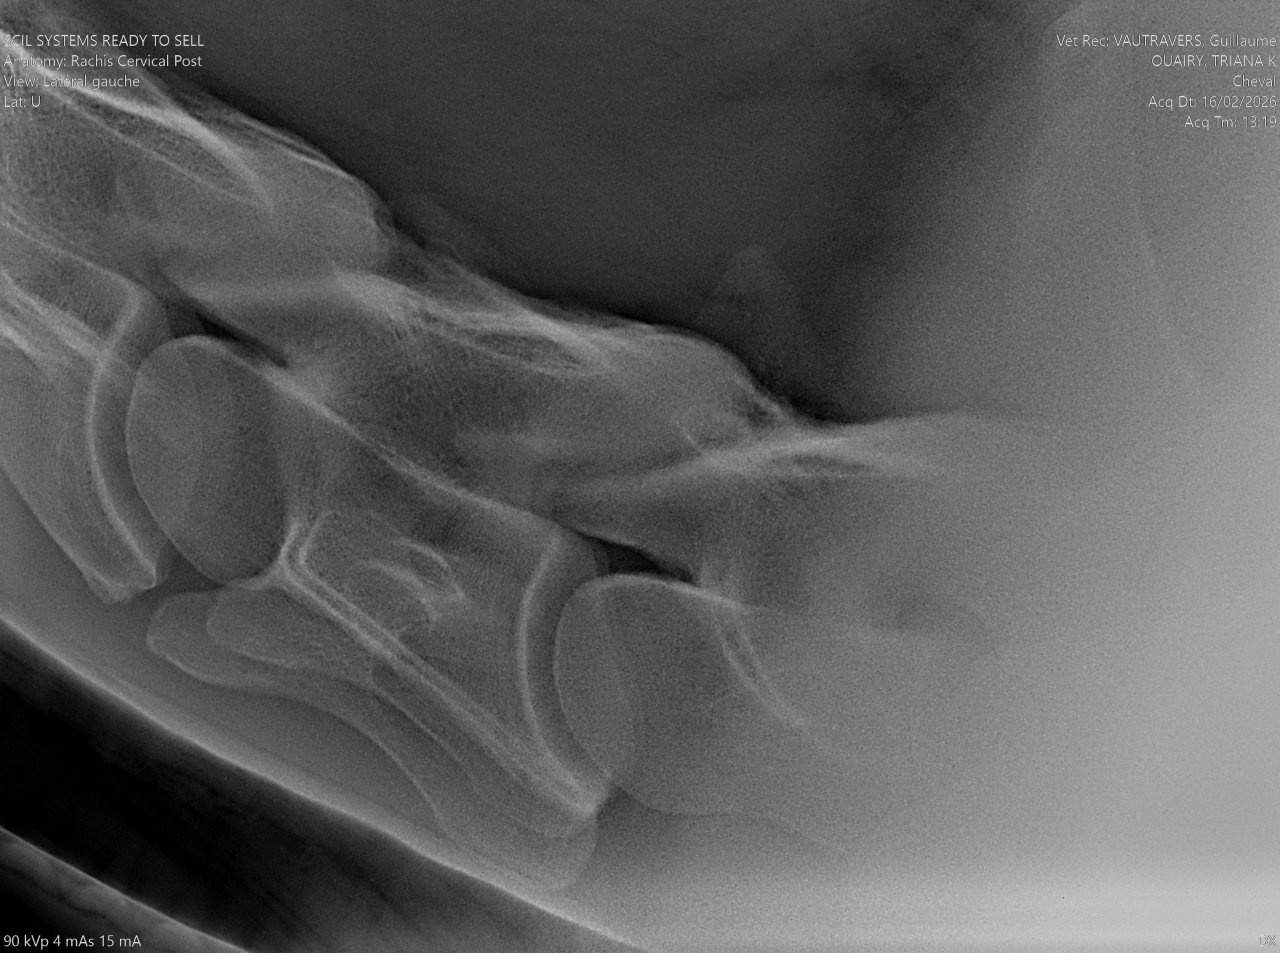

| Dire merci | Bonjour à tous, Ce forum est une mine d'or et peut-être que quelqu'un aura une piste, une idée ou des pouvoirs magiques pour nous aider (oui, j'en suis à ce stade). Ma jument, qui prend 7 ans cette année, ne peut plus tourner à droite au trot. Petit récap de sa vie : Je l'ai acheté à 1 an. Elle avait déjà une démarche particulière des postérieurs mais à la visite véto, on a contrôlé les grassets et RAS. Les vétos ont mis ses allures sur le compte de la croissance. Princesse grandit et chaque année, elle rencontre un problème (blessure, infection bactérienne, problème divers et varié). Je commence le débourrage en extérieur à l'âge de 4 ans mais monte très très peu. A 5 ans, je termine le débourrage aux 3 allures en extérieur mais le travail reste très léger. Je sens déjà que le trot n'est pas son fort. Elle est plus confortable au galop. 6 ans, grave accident ou elle reste couchée des heures sur son côté droit, qui nécrose complètement. On arrive à la fin des 6 ans, je la change de pension, la met au travail en carrière. Une jument qui va beaucoup mieux, qui travaille bien, qui change physiquement. 3 mois de paix. 3 mois ou je me dis : "enfin on va pouvoir profiter". Mais non, fin décembre, elle commence à se défendre quand je monte. Je sens une gène physique mais peut-être que la mise au travail ne lui plait pas. J'axe sur l'extérieur mais les défenses sont aussi présente. Elle refuse de trotter (je peux marcher et galoper). Petit à petit, l'état s'aggrave. Je ne peux plus monter, même à main gauche, j'ai des défenses. L'ostéo passe en Janvier. Ca va mieux à gauche mais toujours la cata à droite. Si je lui demande de tourner à droite au trot, soit elle se lèvre, soit elle prend le galop, soit elle se met complètement de travers pour pouvoir tourner. Mardi 16 février, je la descends en clinique pour un examen locomoteur. Des radios et echos de partout...mais rien. Enfin, pas grand chose. Des petites choses mais rien qui peut expliquer le problème. Il y a une inflammation des grassets, des 2 côtés. Mais le véto pense que ce n'est pas ça. Il me dit de la faire monter par un cavalier expérimenter pour voir si ce n'est pas moi le problème... Je vais vous mettre la vidéo mais non, même avec une monitrice, la jument refuse de tourner et se défend. Ovaires et utérus : RAS Elle commence 10 jours d'anti inflammatoire et je dois la remonter vendredi voir si le problème est toujours présent. Bref, je n'ai aucune piste, je ne sais pas quoi faire. Le véto non plus... Quelqu'un a déjà eu une expérience similaire ?! Un avis sur la question ? |

| Dire merci | @takhan elle tourne en longe. Tu vois quand même une gène mais elle cercle. Elle est suivi dentiste. La dernière visite remonte à juillet 2025. Je charge les photos du dos mais RAS. Un peu d arthrose juvenil bassin et jarret mais stade 1, qui n'explique pas ses défenses. |

| Dire merci | Clemclem99 Bassin et jarrets, il y a de l arthorse juvenil stade 1 Grasset présentant un état inflammatoire des deux côtés. Il a fait toutes les manipulations du bassin, il bouge bien. Je lui ai dis que ma jument était régulièrement tendu sur cette zone, surtout l"hiver mais pour lui, y a rien : ![]() Je lui ai aussi dis que je sentais comme une décharge électrique qui partait de l ilio psoas jusqu'à l'epaule du côté droit quand je montais. Il m'a demandé si j'avais un voltomètre, suis passée pour une folle mais rien dans cette zone![]() Le postérieur droit, elle ne me le donne plus correctement, elle le décale sur le côté Le gauche, il a toujours été particulier, elle le ramène fort sous elle avant de l'étendre pour que je puisse curer |